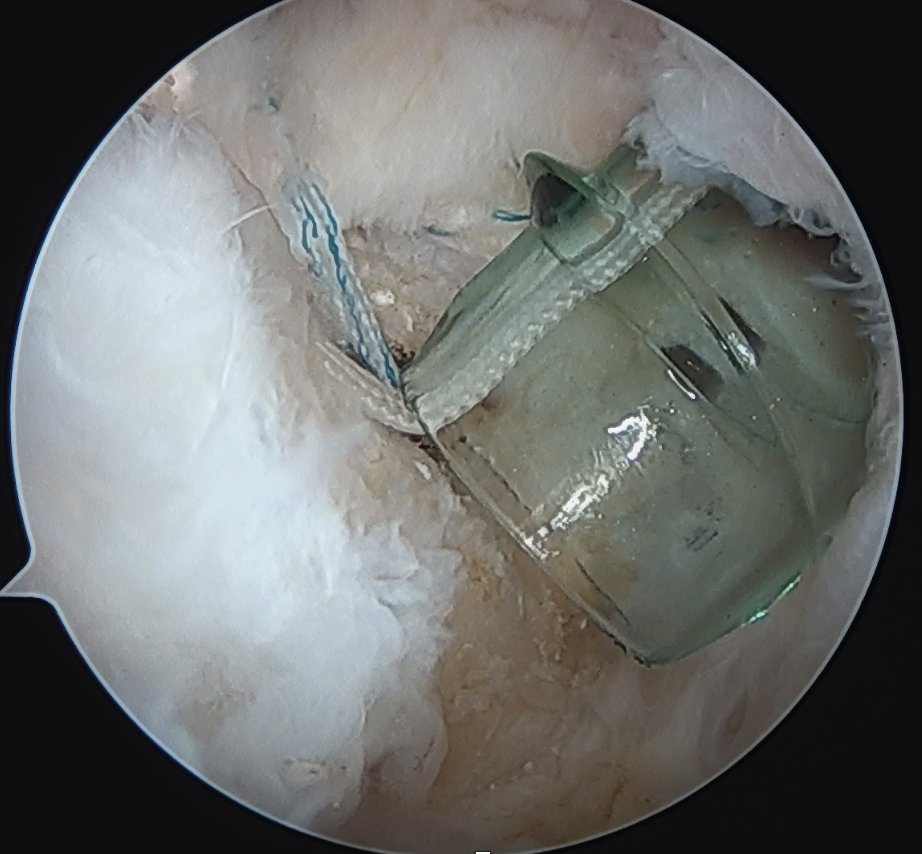

Double row anchors

- medial anchor row at articular margin and tie through medial cuff

- lateral anchor row at lateral footprint used to secure sutures

- increase surface area of cuff repaired to foot print

Trans-osseous equivalent / suture bridge

- cross sutures from medial row to lateral row

- increase contact between cuff and footprint

Double row / suture bridge

- use medial row sutures

- secure in knotless lateral row anchors